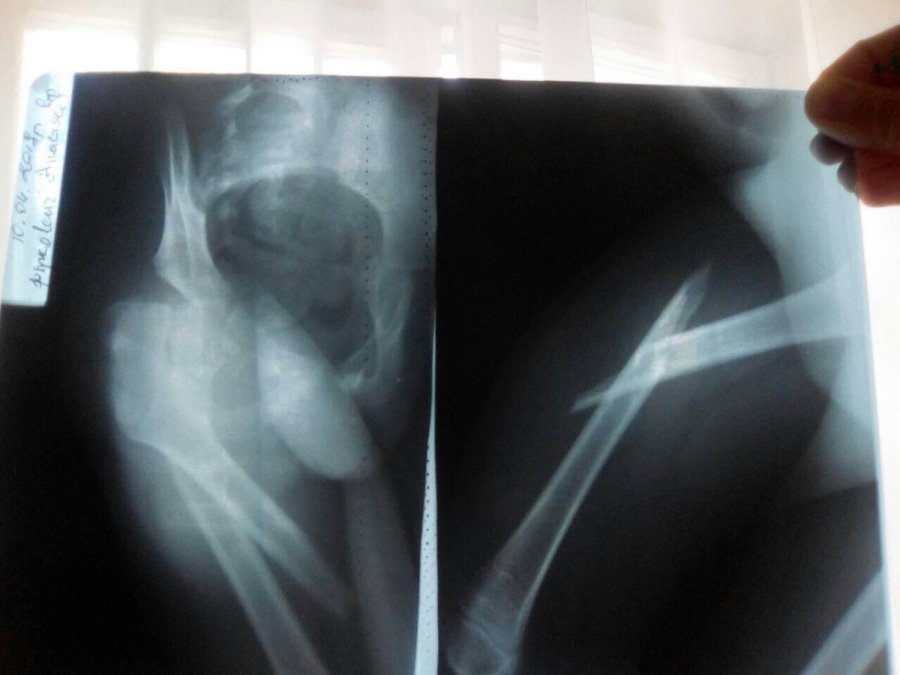

Маленька дівчинка, незважаючи на цілий "букет" діагнозів (ДЦП, епiлепсiя з частими полiморфними припадками, вроджений двобiчний пiдвивих стегон, постiйна косоокiсть лiвого ока і т.д.), має шанс на нормальне життя, - пише Район.Бізнес.

Зазначають, що у квітні реабілітолог, займаючись із дитиною, зламав Насті ногу. Дівчинці потрібна була операція і за допомогою соцмереж вдалося зібрати необхідну суму. Наразі Настя вже відійшла від операції та потребує додаткових, приватних занять, щоб розробляти ніжку. Також вона має пройти декілька курсів масажу, а в мами немає на це коштів.